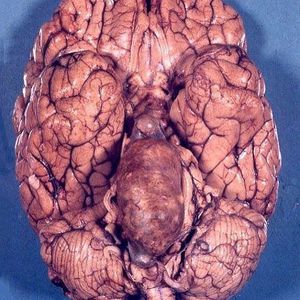

Atherosclerotic aneurysm of the basilar artery.This huge aneurysm of the basilar artery is not congenital, but atherosclerotic. Severe atherosclerosis may gradually weaken the wall of an artery, promoting their aneurysm. The most common example is the abdominal aorta. The aneurysm was not broken and was found at autopsy. It caused noticeable deformation of the anterior surface of the brainstem. The aneurysm was filled with mixed thrombus arranged in several concentric layers. However, there was a light and maintaining blood flow (otherwise there would have been massive brainstem infarction, incompatible with life). Intracranial atherosclerotic aneurysms are much rarer than congenital aneurysms.